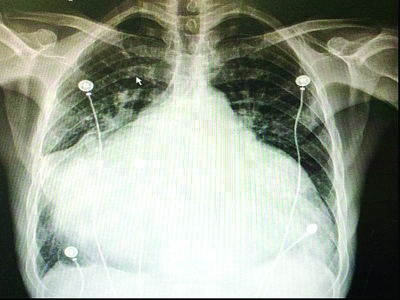

手术前的检查显示,患者心脏已经大如足球,撑满了整个胸膛。

从影像上看,老吴的心脏明显扩大,体积几乎是正常人心脏的3-4倍。尤其是左心房,正常人左心房的直径一般在3.5至4厘米,而患者左心房直径达到了14厘米,左心室也扩大了近一倍。从胸片上看,患者的心脏占胸腔比例高达95%,几乎撑满了整个胸腔,而正常人这个值是小于50%的。扩大的心脏严重压迫了周围的肺组织以及食管,严重影响肺功能,还造成患者吞咽困难。